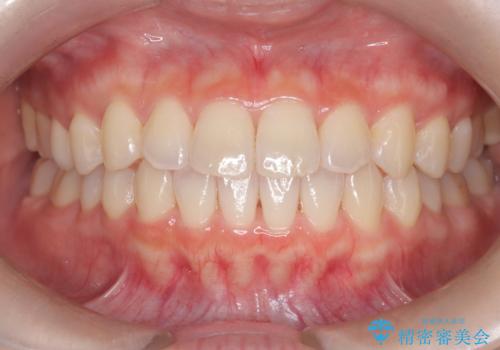

前歯と奥歯のガタガタを矯正で改善

担当医 河口智英